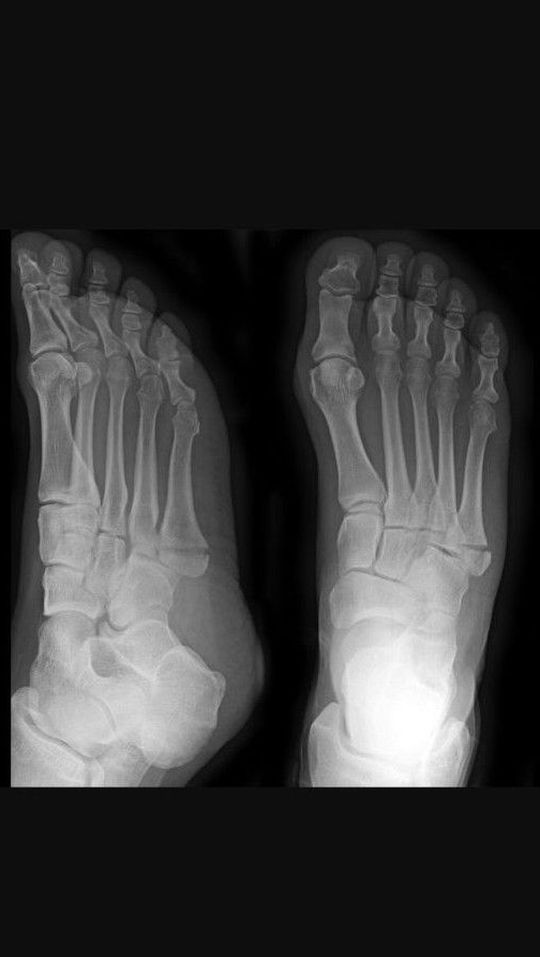

Diagnosis?

Fifth digit has 2 phalanges

Jones fracture?

Is that an older fracture on the fifth metatarsal?

Fifth metatarsal fracture